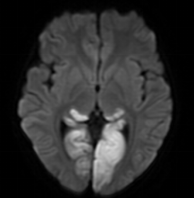

答:確診主要依靠頭顱磁共振檢查。引起兒童腦梗死的原因多樣,某些原因還會誘發(fā)腦梗死的復(fù)發(fā),因此對于腦梗死的患兒需進(jìn)一步評估有無心臟、血管及血液系統(tǒng)的其他危險因素。